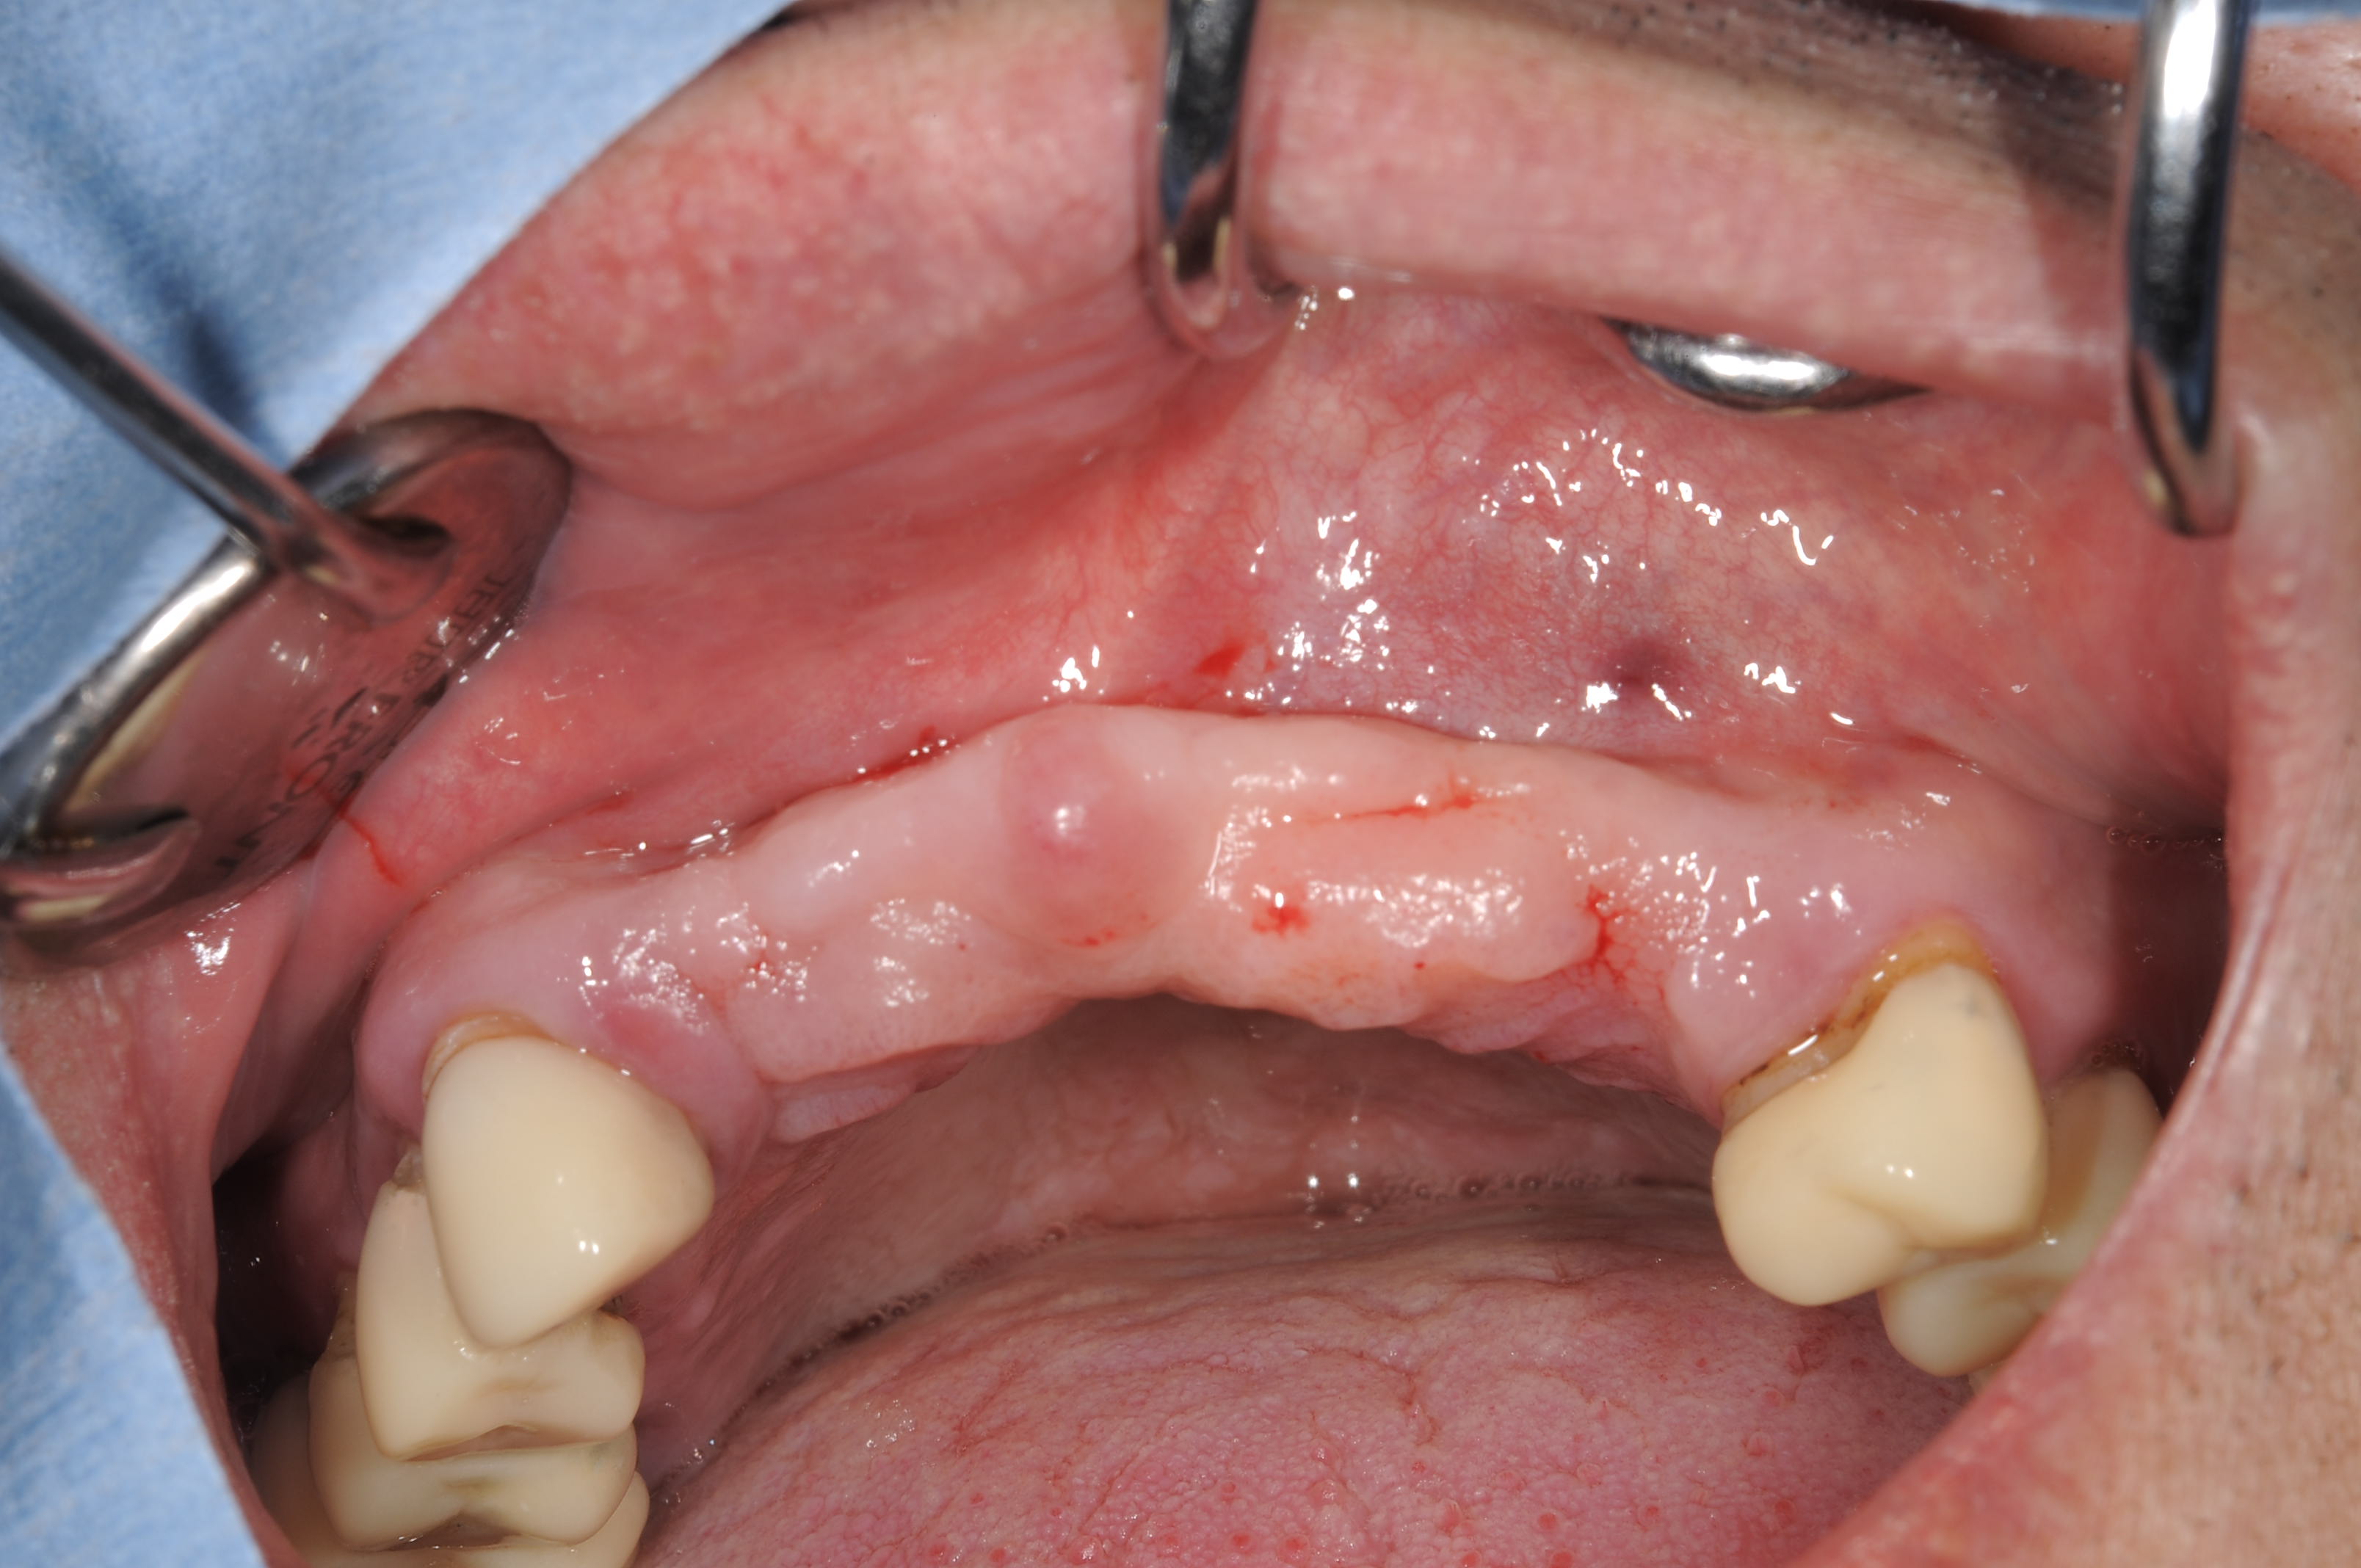

術前の埋入部位ですが、唇側前庭部がくぼんでいます。

やや舌側側に平衡に埋入しました。

裂開したところは、bio-ossと Bioguide でGBRを行っています。